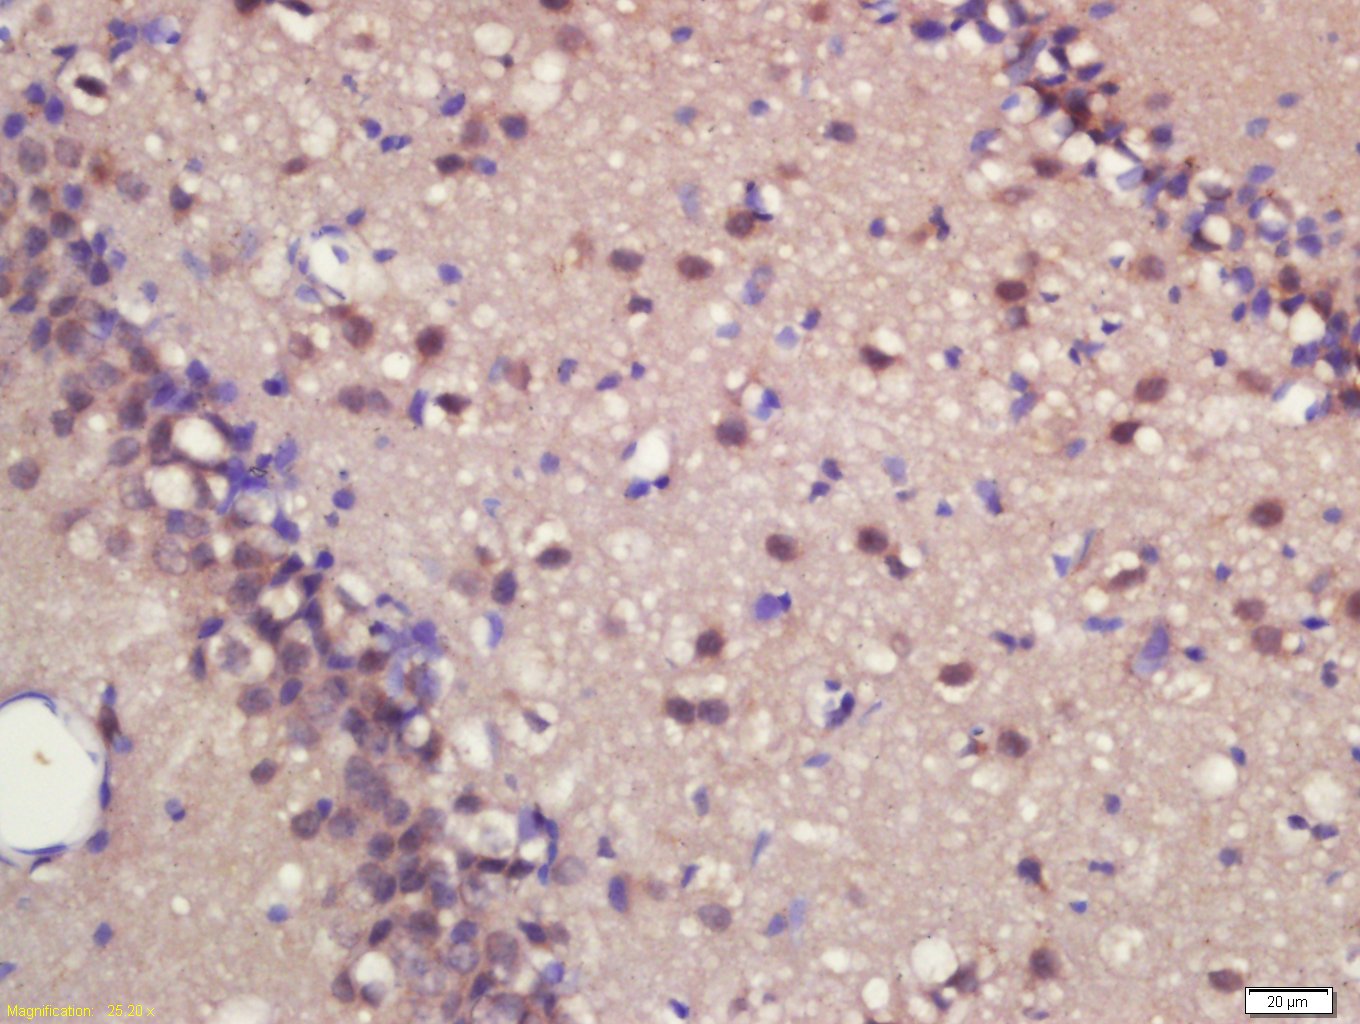

Antigen retrieval: citrate buffer ( 0.01M, pH 6.0 ), Boiling bathing for 15min; Block endogenous peroxidase by 3% Hydrogen peroxide for 30min; Blocking buffer (normal goat serum,C-0005) at 37℃ for 20 min;

Incubation: Anti-MASH1 Polyclonal Antibody, Unconjugated(bs-1155R) 1:200, overnight at 4°C, followed by conjugation to the secondary antibody(SP-0023) and DAB(C-0010) staining